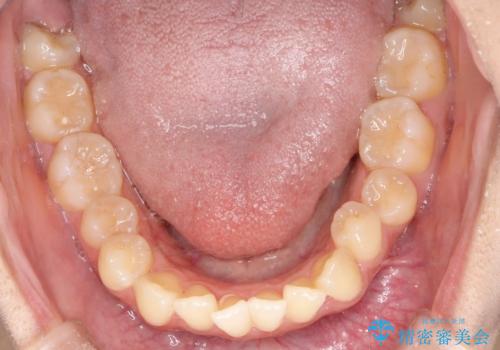

- 患者様は左上の八重歯を気にされて来院されました。八重歯による歯列の乱れだけでなく、翼状捻転(歯がねじれるように生えている状態)も見られました。目立たない矯正を希望されていたため、**インビザライン(マウスピース矯正)**を選択し、左上の小臼歯を抜歯してスペースを作りながら歯を並べる治療計画を立てました。しかし、治療の途中で翼状捻転の改善が十分に進まなかったため、患者様の希望も踏まえ、上顎のみワイヤー矯正に変更することとなりました。

治療開始時はインビザラインを使用し、全体の歯並びを整えながら抜歯スペースを活用して歯を後方へ移動させました。しかし、左上の八重歯のねじれが強く、マウスピースのみでは十分にコントロールできないことが判明。そこで、より細かく歯を動かすために上顎のみワイヤー矯正へ切り替えました。ワイヤー矯正によって翼状捻転も改善し、最終的にバランスの取れた歯並びと噛み合わせを実現。患者様からは「長い治療だったけれど、しっかり整って満足」と嬉しいお言葉をいただきました。